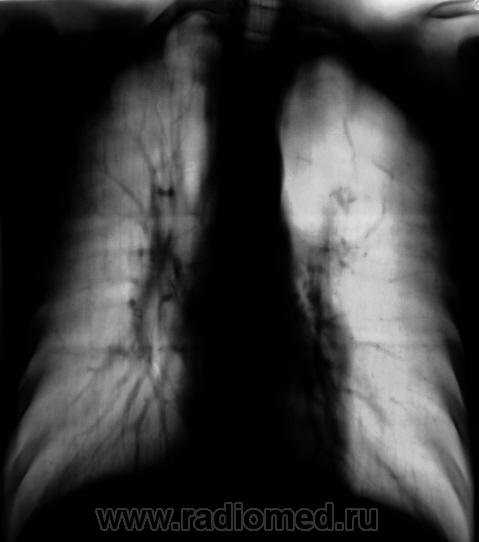

Пациент, подросток направлен из детского отделения на рентгенографию грудной полости с диагнозом "Правостороняя верхнедолевая пневмония". Как показал анализ рентгенограммы органов грудной полости в прямой стандартной проекции, исследование рентгенографией "по поводу пневмонии" не ограничилось.

Гипоплазия верхней доли левого лёгкого. Гипоплазия левой легочной артерии или её ветвей.

Явная аномалия развития ветвей левой лёгочой артерии. На основании каких признаков, вы думаете о гипоплазии верхней доли левого лёгкого?